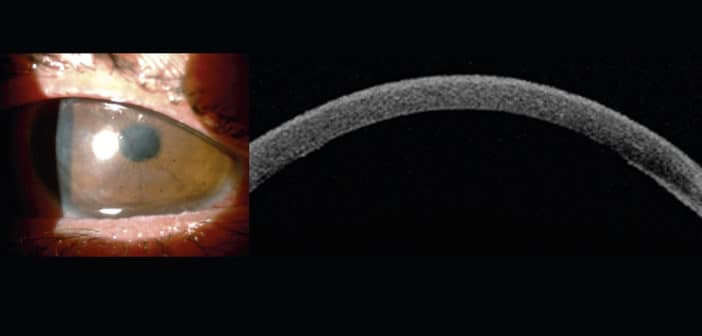

Depuis près de 10 ans, la greffe endothéliale pure (DMEK, Descemet Membrane Endothelial Keratoplasty) a pris une place prépondérante dans nos options de prise en charge des pathologies cornéennes. Elle représente désormais dans notre pratique – et de loin – la principale indication chirurgicale dans les œdèmes de cornée. Qu’avons-nous appris pendant ces 10 ans ?

Dans une méta-analyse publiée début 2019 incluant une dizaine d’études évaluant les DMEK et les DSAEK (Descemet Stripping Automated Endothelial Keratoplasty) dans les dystrophies de Fuchs, Marques et al. retrouvent une meilleure acuité visuelle corrigée dans les DMEK versus les DSAEK (646 et 947 yeux inclus respectivement), ainsi qu’un risque de rejet réduit de 60 % dans les DMEK [1]. La satisfaction des patients était également plus élevée après DMEK. En revanche, le nombre de réinjections de bulle d’air était significativement plus élevé dans les DMEK. Une revue Cochrane de 2018 retrouve une tendance similaire [2]. Dans notre série, près de 85 % des patients opérés de DMEK sur une simple dystrophie de Fuchs récupèrent 8/10 ou mieux d’acuité visuelle [3].

Les principales indications de la DMEK restent les œdèmes cornéens “simples” secondaires à la dystrophie de Fuchs ou ceux du pseudophaques. Cependant, les indications se sont aujourd’hui élargies et incluent aussi bien les anciennes greffes transfixiantes décompensées, les DSAEK qui n’ont pas bien fonctionné ou les yeux plus complexes, vitrectomisés, aphaques, avec antécédents de chirurgie du glaucome ou même en cas de fibrose stromale antérieure ou postérieure. Si la chirurgie est plus complexe dans ces dernières indications, les résultats peuvent être spectaculaires.